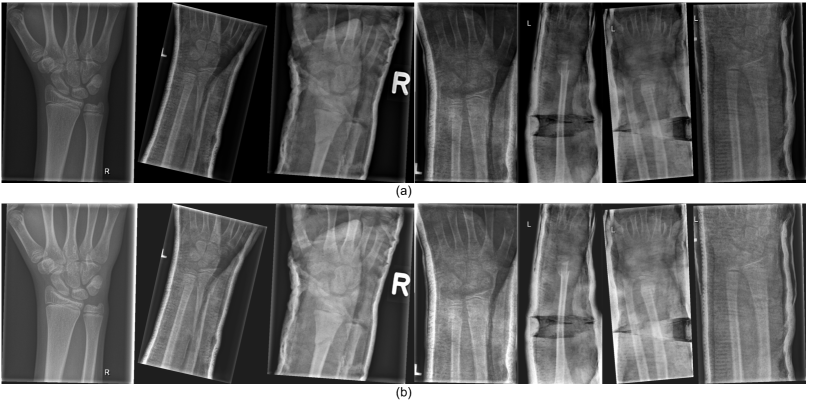

During the model training process, data augmentation is employed in this work to extend the dataset. Specifically, we adjust the contrast and brightness of the original X-ray image to enhance the visibility of bone-anomaly. This is achieved using the addWeighted function available in OpenCV (Open Source Computer Vision Library). The equation is presented below:

| (1) |

where and are the two input images of the same size respectively, represents the weight assigned to the first input image, denotes the weight assigned to the second input image, and represents the scalar value added to each sum. Since our purpose is to adjust the contrast and brightness of the original input image, we take the same image as and respectively and set to 0. The value of and represent the proportion of the contrast and the brightness of the image respectively. The image after adjusting the contrast and brightness is shown in Figure 3. After comparing different settings, we finally decided to set to 1.2 and to 30 to avoid the output image being too bright.